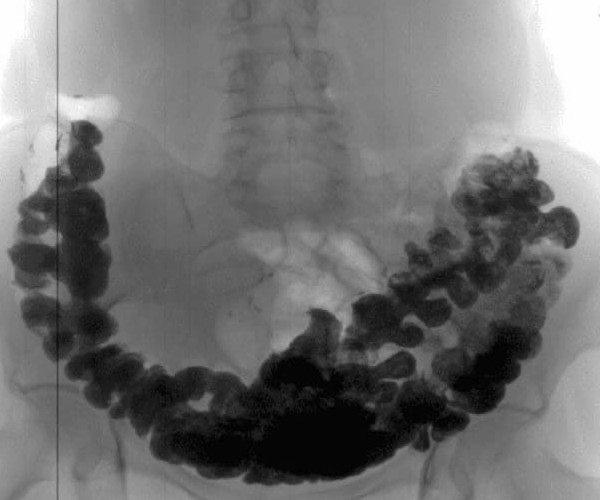

Tilstanden i tarmane mine etter ein kur med Lulutox Tea.

Under eit besøk hos spesialisten stadfesta han resultatet: forstoppinga hadde verkeleg forsvunne heilt! Og utan å skade mikrofloraen. Så det ser ut til at alt gjekk bra, utan biverknader. Operasjonen blei straks avlyst. Eg har ikkje ord for å skildre kor glad eg var då! Eg kjende ei utruleg letting! Dei som har blitt kvitt kronisk forstopping vil heilt sikkert forstå meg.